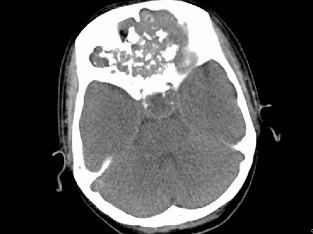

问题 男,26岁,进行性鼻腔阻塞、流涕来院就诊,近两年持续性头痛、头晕.如图所示筛窦区占位灶应诊断为 ( )

选项 A、骨结核伴左上颌窦炎 B、骨纤维异常增殖症伴左上颌窦炎 C、软骨瘤伴左上颌窦炎 D、骨化性纤维瘤伴左上颌窦炎 E、脊索瘤伴左上颌窦炎

答案 C